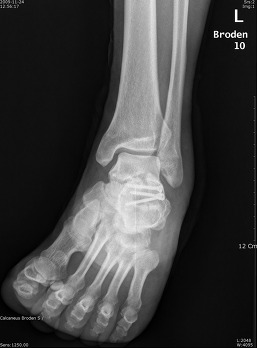

Broden view

촬영목적 : Subtalar joint의 골절시(comminuted fracture) 관절의 관련 여부를 관찰

촬영자세 : Supine 자세로 다리와 카세트 중앙은 일치하도록 하며,internal oblique자세에서 발목관절이 90˚ 굽힌상태를 유지하도록 발을등쪽으로 굽힌다.

중심선 :  cephalic 10˚ ,20˚, 30˚, 40˚ 로  Lateral malleolar에서 아래앞쪽으로 2~3Cm 떨어진지점에 입사한다

촬영Point : Subtalar Joint가 열려져 나타나며,10˚에서는 뒤쪽관절면의 뒷부분,20˚~30˚에서는 Sustentaculum(재거돌기)과 talus(거골)사이의 관절,40˚에서는 앞부분이 잘나타나야한다.